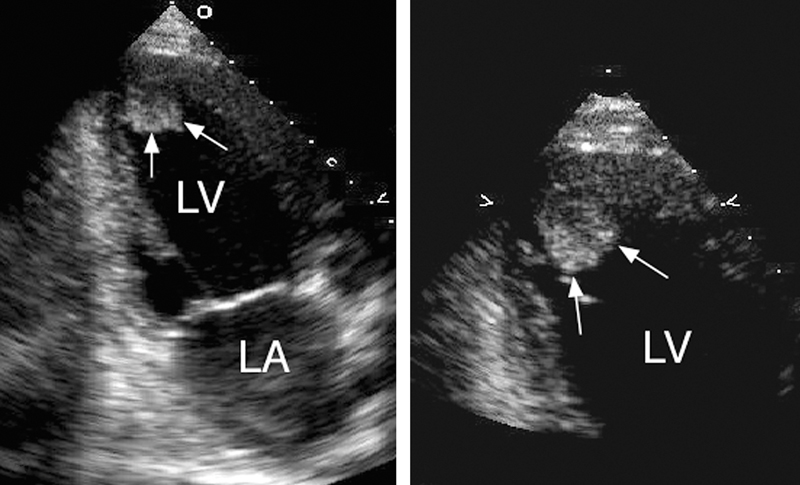

فحوصات تشخيصية لبعض امراض القلب والشرايين التاجية